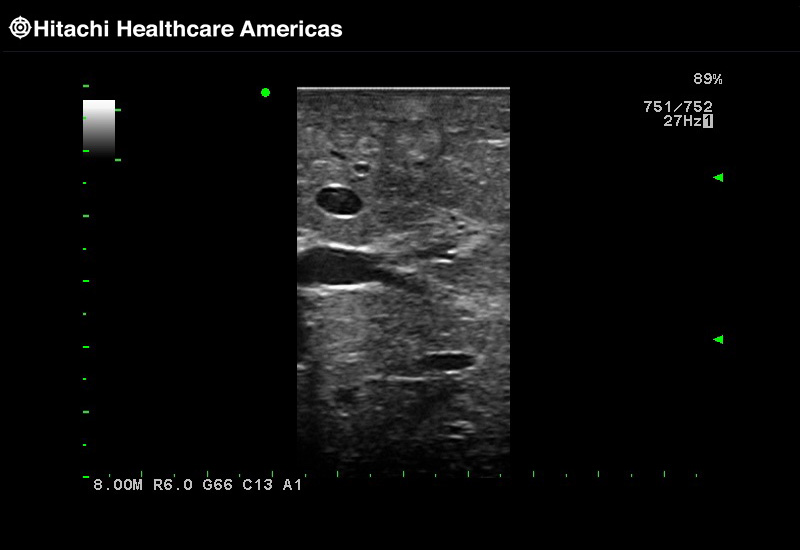

The Fujifilm Healthcare transducer utilizes the full benefits of the Wrist Articulation™ of the robotic instruments to capture real-time ultrasound imaging even at complex angles and difficult-to-reach areas.

Our smallest footprint allows for enhanced contact in tight spaces

Our newest probe, the L51K allows the surgeon access to difficult-to-reach areas that no other probe on the market can go. The unique design and proximal location of the attaching mechanism provides full wrist articulation and easier grasp and release.

Full wrist articulation with optimized functional length.

A critical function of robotic ultrasound guidance is tumor margin identification. Fujifilm's family of robotic probes all have the optimum location of the attaching mechanism that allows for full wrist articulation of the probe. The result is an increased confidence that the tumor margins have been completely identified.